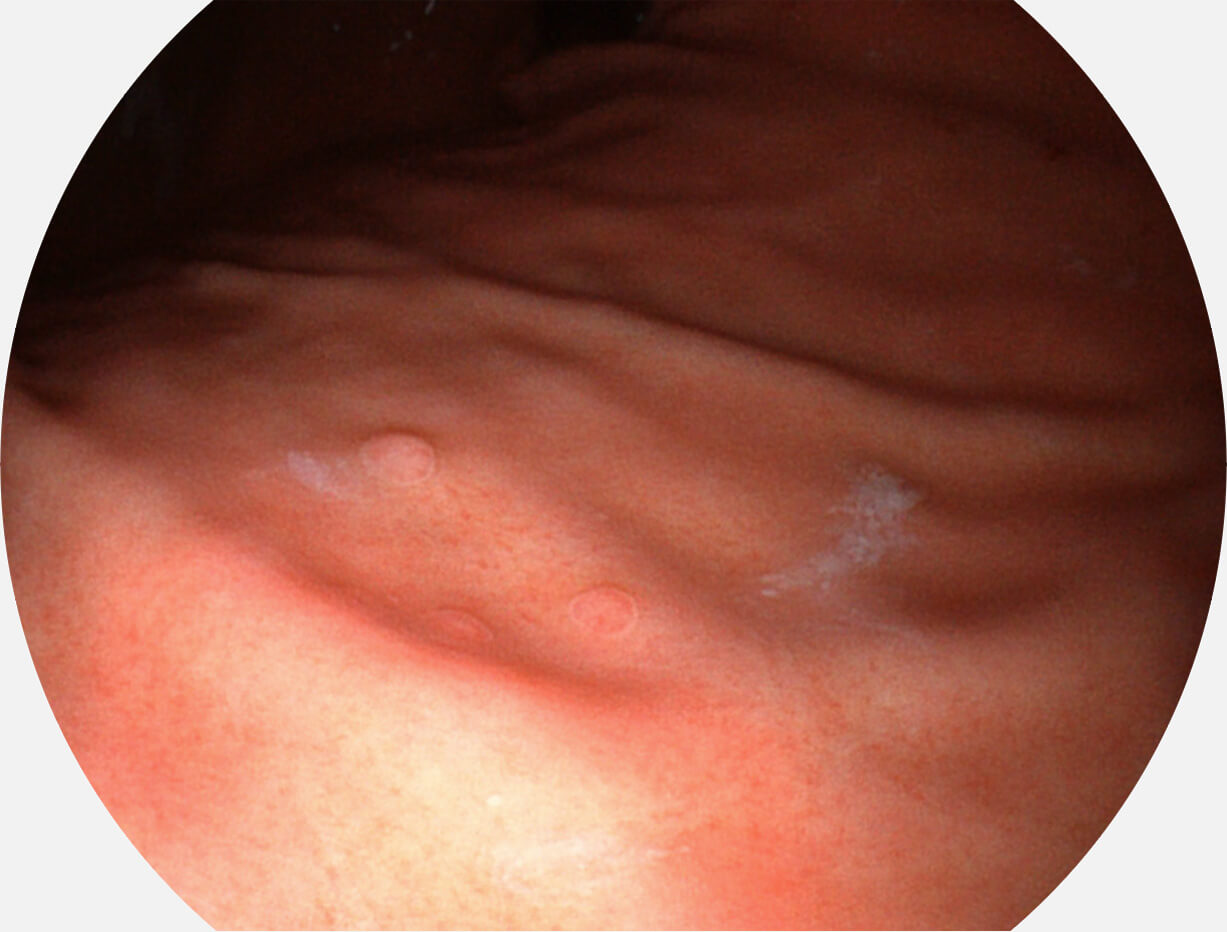

强调浅层黏膜结构的同时,保证照明亮度和提升浅层微血管与中层血管颜色对比度,病变边界更清晰。

VIST图像